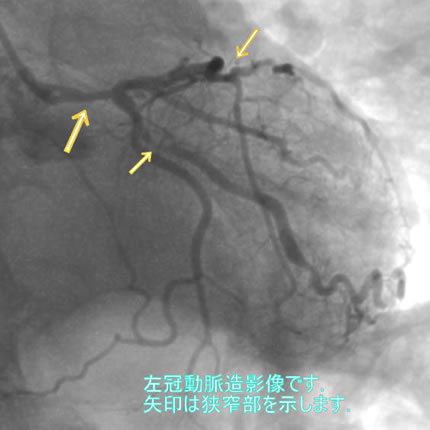

図3-1

3番目の患者さんは70才の男性です。危険因子は高血圧、喫煙です。図3-1から3-5までは全てこの患者さんの画像です。

色々とお目にかけましたが、動脈の硬化により動脈が狭くなったり(狭窄)、太くなる(瘤状変化:りゅうじょうへんか)のがお解りになられたと思います。